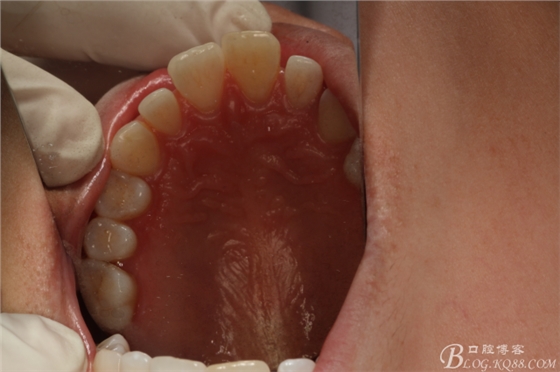

圖1.患者術(shù)前的口內(nèi)正面像:11和21前突、11和12有間隙

圖2.腭側(cè)口內(nèi)像觀:腭側(cè)平坦,未捫及隆起